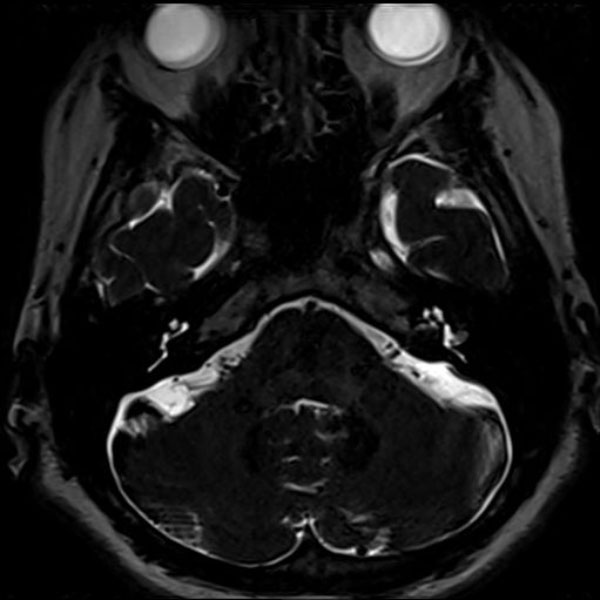

587

大阪府の病院

'26年4月

50代

左顔面痙攣

術後血管撮影